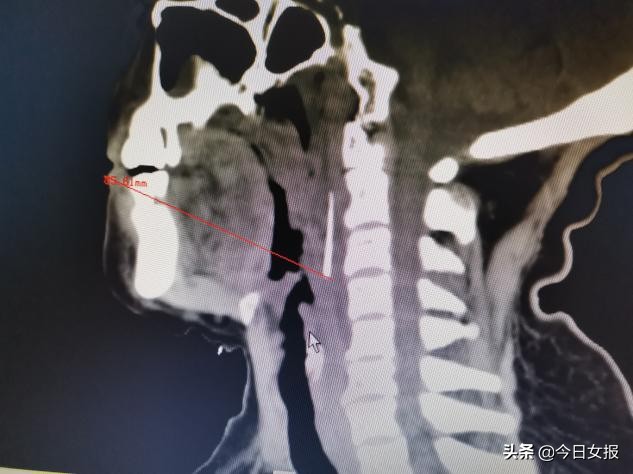

凌科技副主任医师接诊后查看CT影像发现,异物尖端位于老人口腔与食道入口上端,可谓“深藏不露”。手术团队讨论认为,如果经口腔入路切开咽后壁粘膜,由浅入深探查异物,虽然距离近,但异物小,位置隐匿,很可能寻找失败。

综合考虑上述因素后,5月4日,凌科技副主任医师团队在经口喉内镜辅助下,精准定位异物,切开咽侧壁顺利探查到异物,成功取出残余的3cm长钢针。手术耗时仅30分钟,术中几乎没有出血。